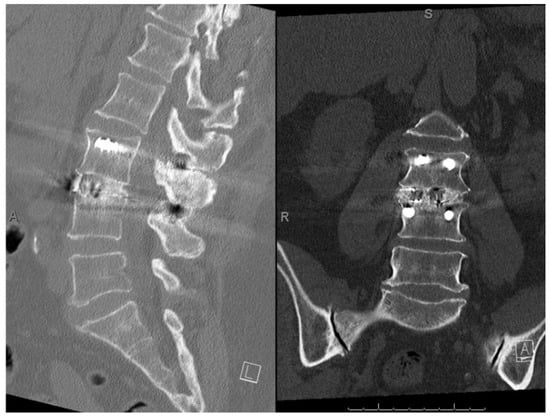

3.2. Radiographic Fusion Outcomes